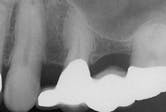

Gemination

2. Identify the most likely radiographic appearance of a geminated tooth:

3. Identify the treatment for a geminated tooth:

4. Identify the dental anomaly that may be confused with gemination: